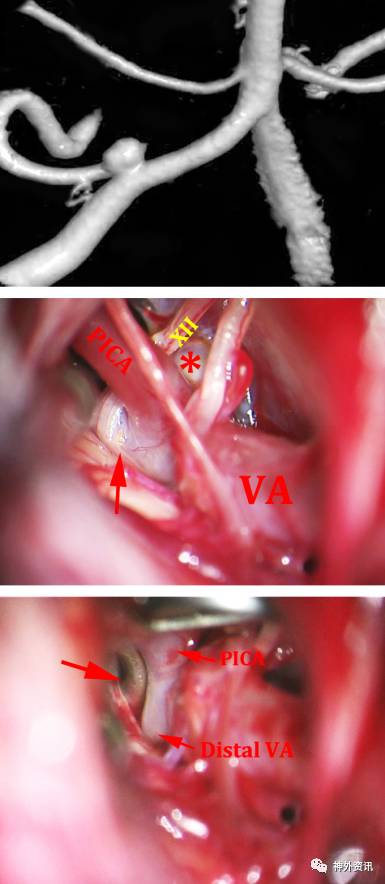

图11:PICA动脉瘤可以根据其所处的解剖结构直接夹闭。椎动脉近心端临时阻断(上图),椎动脉远心端用红色箭头标记(下图)。

图12:右侧PICA动脉瘤使用直角动脉瘤夹夹闭(上图);远端和近端需要临时阻断,原因在于怀疑可能是假性动脉瘤(中图);最终夹闭动脉瘤(下图)。

图13:更加典型的PICA动脉瘤被完全夹闭,使用直角跨血管夹(上图);椎动脉远端用红色箭头表示,动脉瘤使用*标记(中图);舌下神经与PICA、VA的关系被显示出来;最终动脉瘤被夹闭,箭头所示为动脉瘤夹所在位置(箭头,下图)。